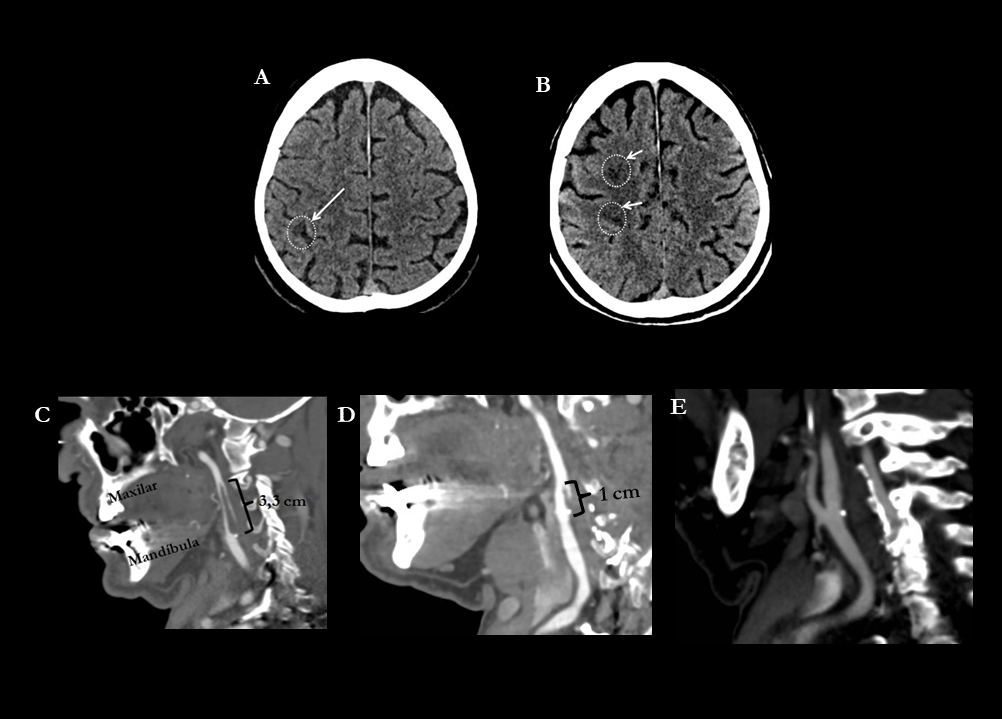

A y B. TC craneal basal. Cortes axiales.

Las fechas señalan 3 lesiones hipodensas de nueva aparición a nivel de la circunvolución postcentral derecha y en corona radiata ipsilateral, compatibles con infartos recientes en el territorio de la ACM derecha

C. Angio-TC realizado el mismo día. Reconstrucción sagital. En el interior de la arteria carótida interna derecha se evidencia un defecto de repleción compatible con trombo flotante de 3,3 cm.

D. Angio-TC realizado 7 días después. Se objetiva una disminución significativa del trombo flotante, pasando de los 3,3 cm de longitud al 1 cm.

E. Angio-TC realizado 14 días después. Práctica resolución del trombo en el interior de la carótida interna. Únicamente se visualiza una pequeña placa de ateroma fibrocálcica que no ocasiona estenosis.